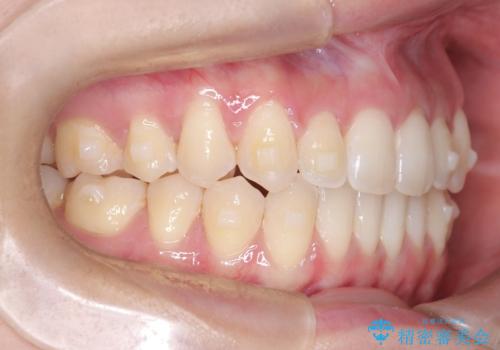

再矯正 前歯のガタツキをマウスピース矯正で治療したい

- 前に矯正治療をしたが、後戻りしてガタツキが出てきたので、治したいとのことで来院されました。

ワイヤー治療とマウスピース矯正、2通りの治療を提案させていただき、マウスピース矯正治療を希望されましたので、インビザラインによる治療を開始しました。

前歯のガタツキを改善する治療法として、マウスピース矯正が適していることが多いです。

マウスピース矯正は、金属製のブラケットやワイヤーを使用せずに、透明なマウスピースを装着して歯を移動させる方法です。そのため、目立たず、痛みも少ないです。